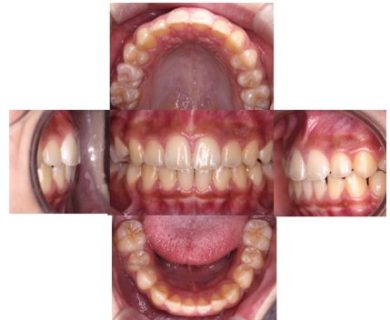

2年6か月後→

8歳6か月(お母さん:娘の出っ歯と前歯の凸凹を治してあげたい)11歳2か月